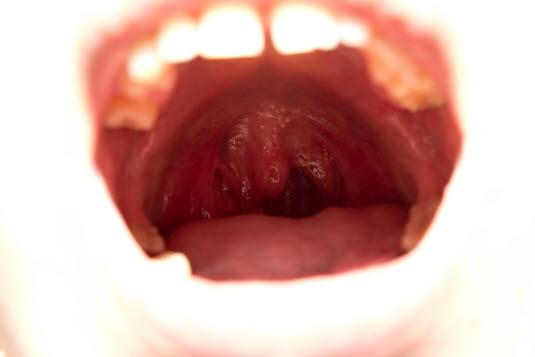

Ved vanlig halsundersøkelse kan legen inspisere halsmandlene og se om det har utviklet seg halsbyll. Dette viser seg ved betennelse ovenfor mandlen med det resultat at halsmandelen og drøvelen forskyves over mot den friske siden. Et typisk tegn er at en pasient med halsbyll nesten ikke klarer å gape opp ved undersøkelsen.